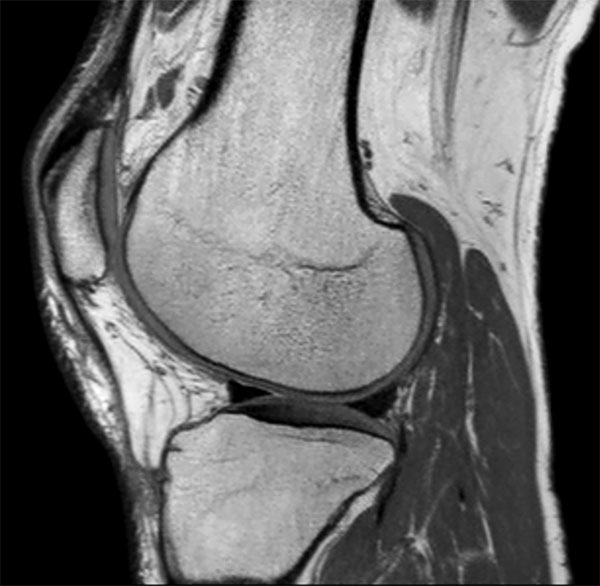

Comprehensive 3D knee imaging with MSK VIEW